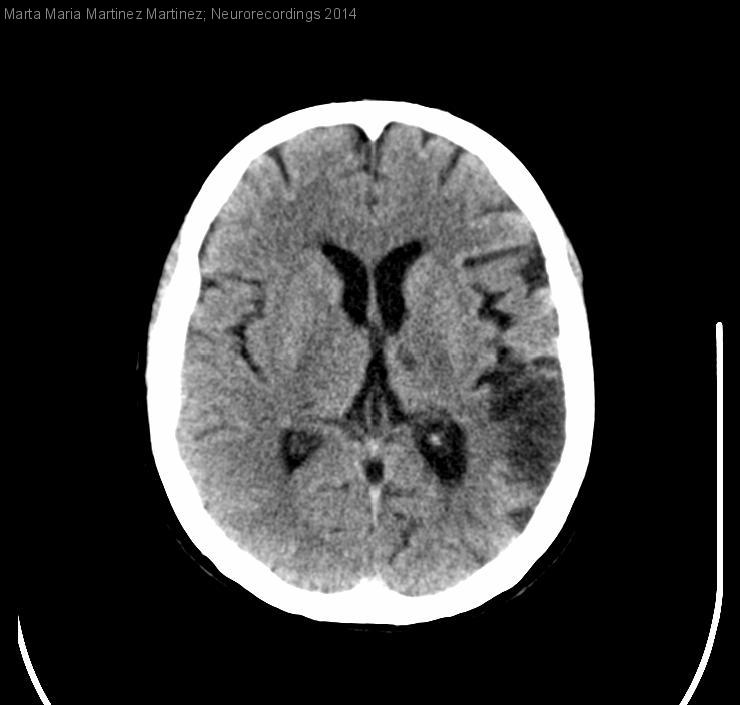

INFARTOS CEREBRALES EMBÓLICOS MÚLTIPLES

Mujer | 60 años

Diagnóstico final: INFARTO CEREBRAL AGUDO EN TERRITORIO ACM DERECHA DE ORIGEN CARDIOEMBÓLICO. INFARTOS CEREBRALES ANTIGUOS TALÁMICO Y PARIETAL IZQUIERDOS Y CEREBELOSO IZQUIERDO DE ORIGEN CARDIOEMBÓLICO.